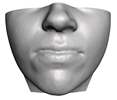

2.5.2. Soft Tissue

2.6. Textured Output Visualization